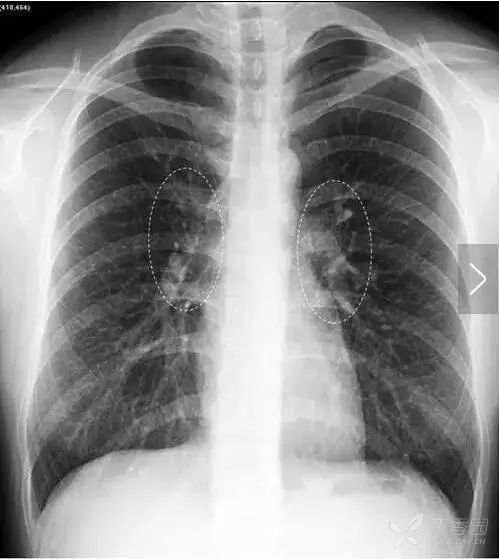

胸部X线平片所指的肺门即肺动静脉及气管等进出肺的部位的诸结构的投影,当然,左、右肺分别有各自的肺门(图8)。

图8 左、右肺门(虚线椭圆范围内)为肺动静脉及气管等进出肺的部位诸结构的投影 。

右肺门上下部分形成一钝角叫右肺门角(图9),右肺门处病理策划的出现可以导致右肺门角消失。右肺门下半部分主要是右下肺动脉干(图10)。

图9 右肺门上下部分形成一钝角叫右肺门角 ,一般为钝角。